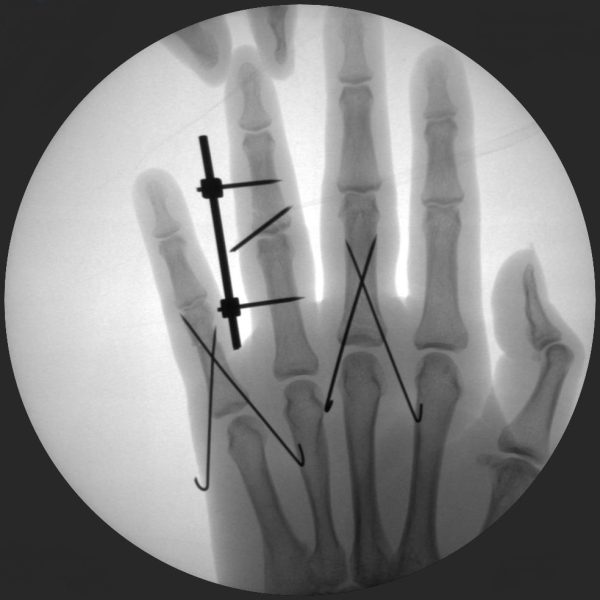

CRIF - Closed reduction internal fixation

ORIF - Open reduction internal fixation

Clinical Evidence

Skan-C is a great C-arm for orthopaedic treatments for several reasons